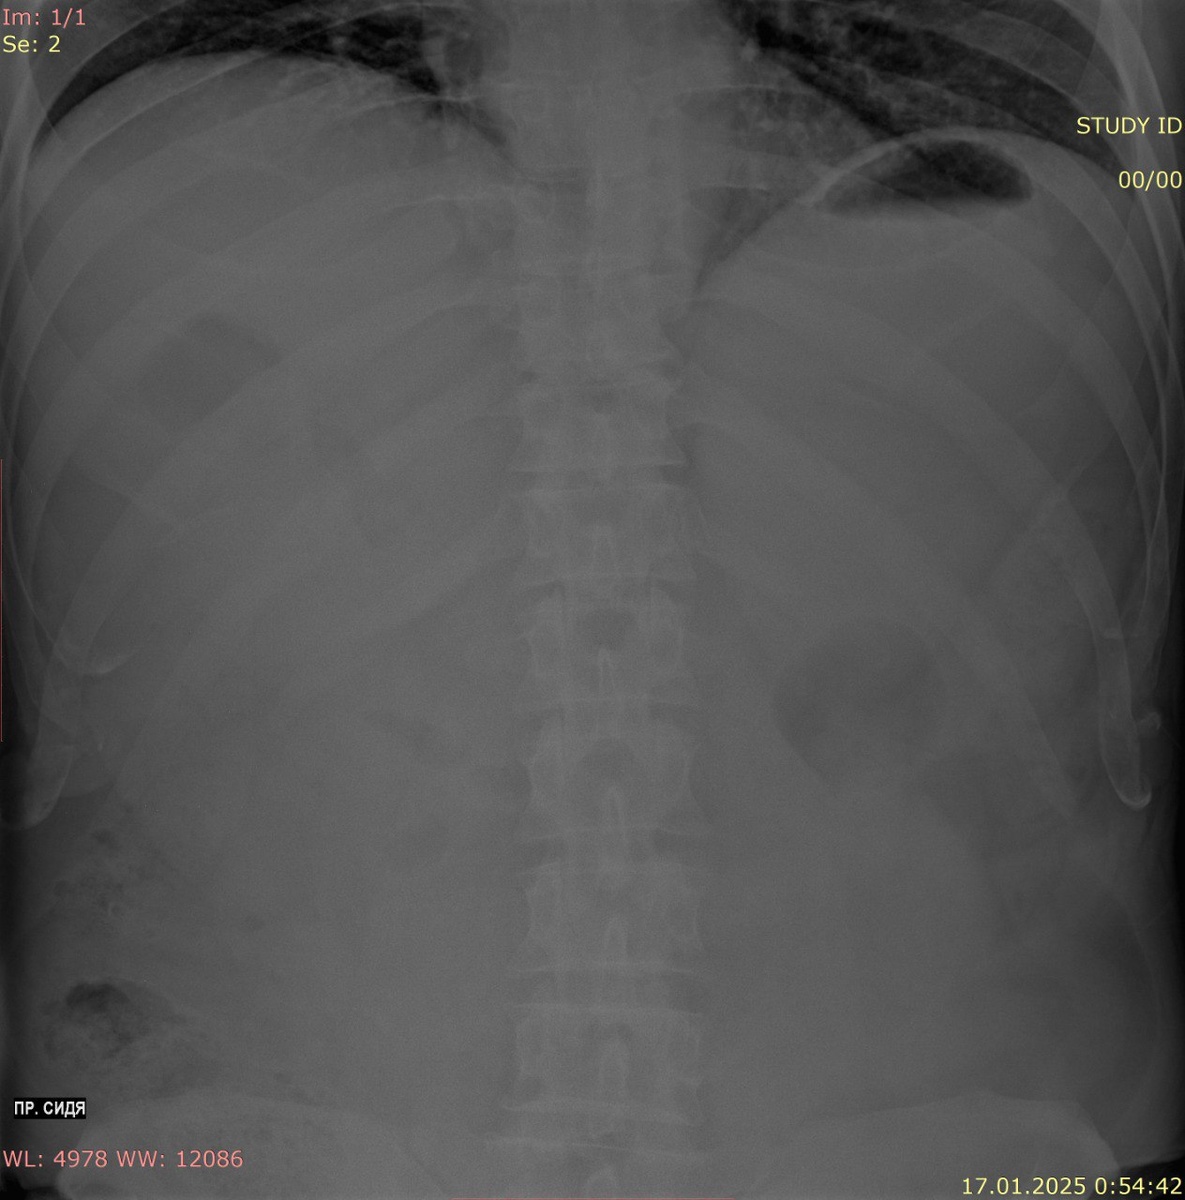

6. Свободный воздух и жидкости: Нормально свободный воздух в брюшной полости обычно отсутствует, но его наличие может указывать на перфорацию органа. Также на изображении может быть видна жидкость, что свидетельствует о наличии асцита или геморрагии.

Брюшная полость в основном состоит из органов пищеварительной системы, включая желудок, тонкий и толстый кишечник, а также органы мочевыделительной и репродуктивной систем. Размещение этих органов имеет свои собственные анатомические особенности.

В правой верхней части могут быть видны печень и желчный пузырь, тогда как в левом верхнем квадранте располагается селезенка. Почки находятся на уровне L1 (верхний полюс), и на рентгеновских снимках они выглядят как парные тени. Важным аспектом является то, что на рентгеновских снимках также может быть видно количество свободного воздуха или жидкости, что может выявить наличие патологий в брюшной полости.